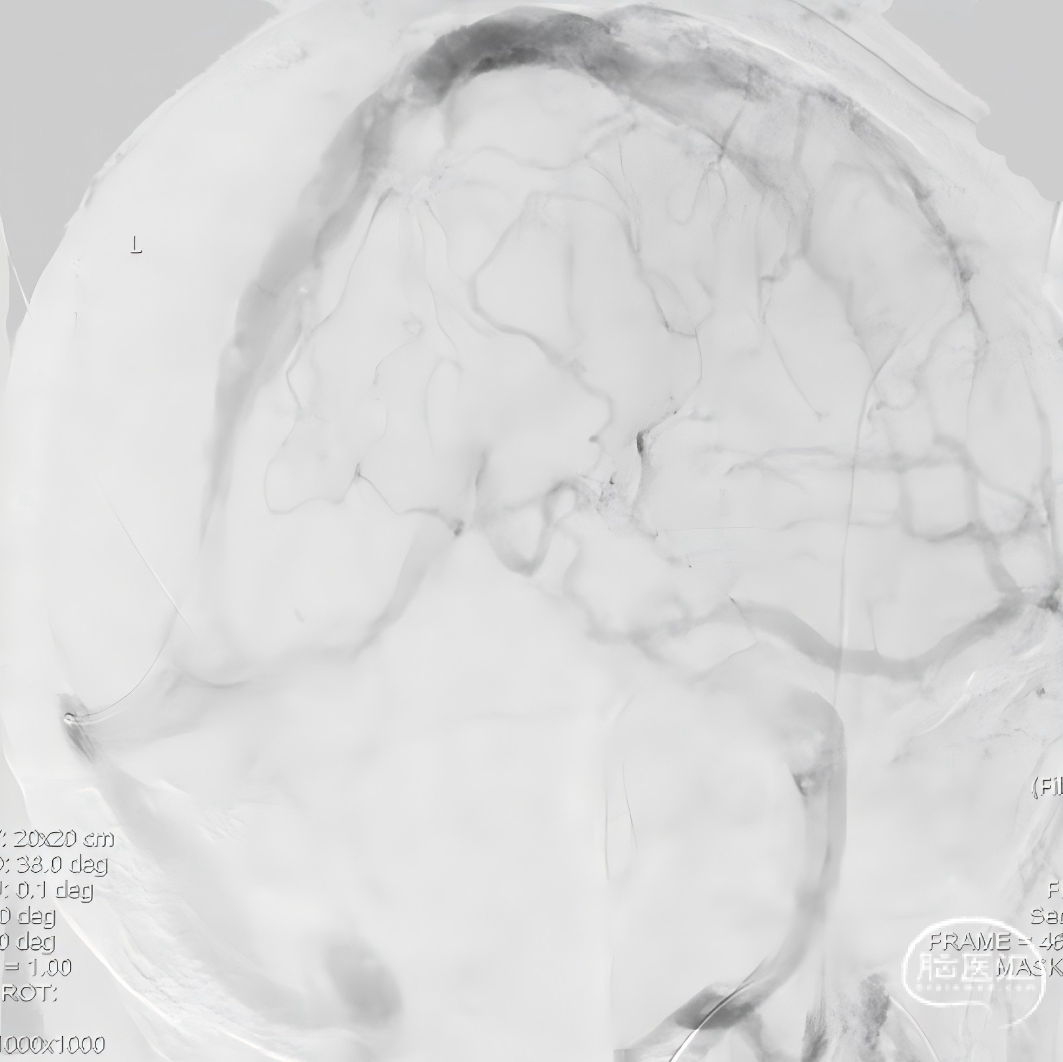

球扩后造影,上矢状窦接触溶栓尿激酶20万U。

球囊扩张和接触溶栓后,再次经中间管反复抽吸后复查造影。

再次给予尿激酶10万U后复查造影。

再次给予球囊扩张,球扩后复查造影。

第二次术后次日复查头CT,置管溶栓3天后(4月6日)拔除微导管及静脉鞘,复查头颅MRV。